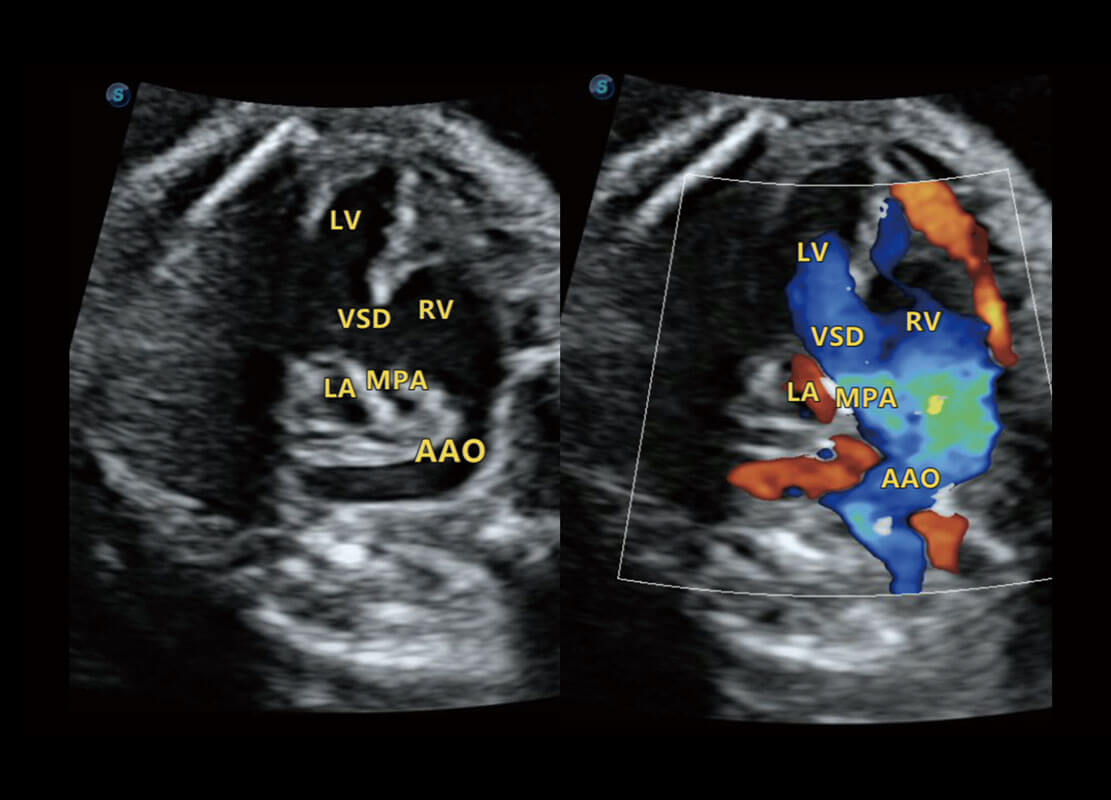

胎心筛查

P60搭载一系列胎儿心脏成像技术,实现精细的胎儿心脏评估。

• 右室双出口

• 胎心容积成像